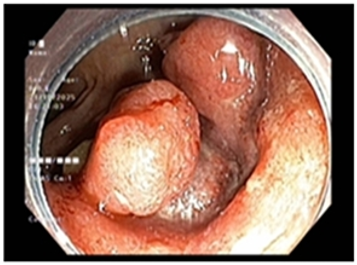

Ca lâm sàng: Ung thư đại tràng ở bệnh nhân 15 tuổi

GS.TS Mai Trọng Khoa; BSNT Hoàng Mạnh Đức, Ths Bùi Quang Lộc , PGS.TS Phạm Cẩm Phương, Bsck II Hoàng Anh, Trung tâm y học hạt nhân và...